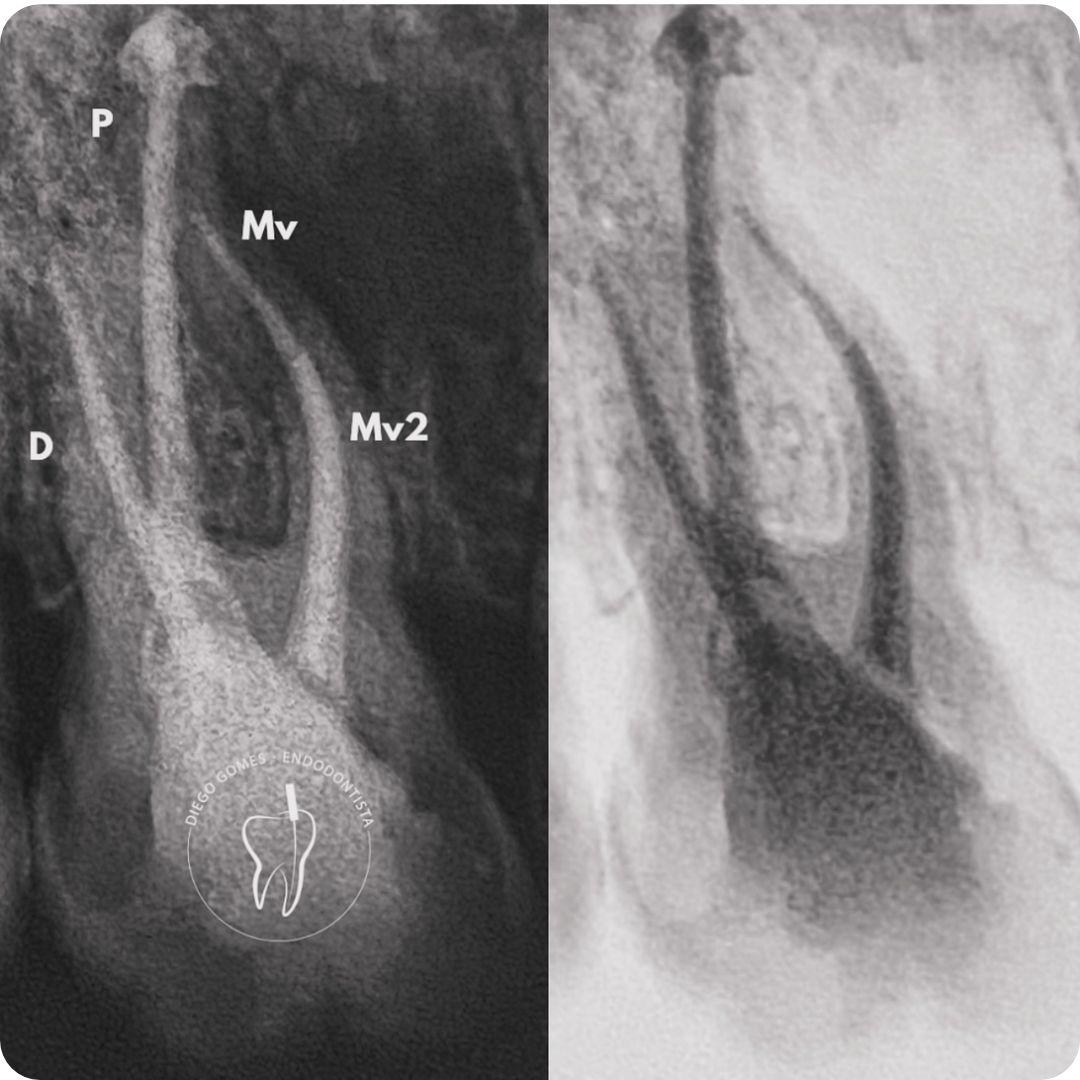

Dr. Diego Gomes é cirurgião-dentista graduado pelo centro universitário cesmac, especialista em Endodontia (ABO-Recife) e pós-graduado em Prótese Fixa, com atuação voltada para o alívio da dor, a preservação dos dentes e o cuidado integral do paciente.

Seu trabalho é baseado em diagnóstico clínico e radiográfico criterioso, uso de tecnologia e atenção individualizada. Com uma abordagem técnica precisa e humanizada, realiza o tratamento completo, incluindo procedimentos preventivos, tratamento de canal e a reabilitação do dente, permitindo que ele volte à sua função por meio de restauração em resina composta ou coroa em cerâmica e, quando necessário, pino de fibra de vidro, sempre com foco na qualidade de vida e no bem-estar.

● Tratamento e retratamento de canal

● Resolução de casos complexos